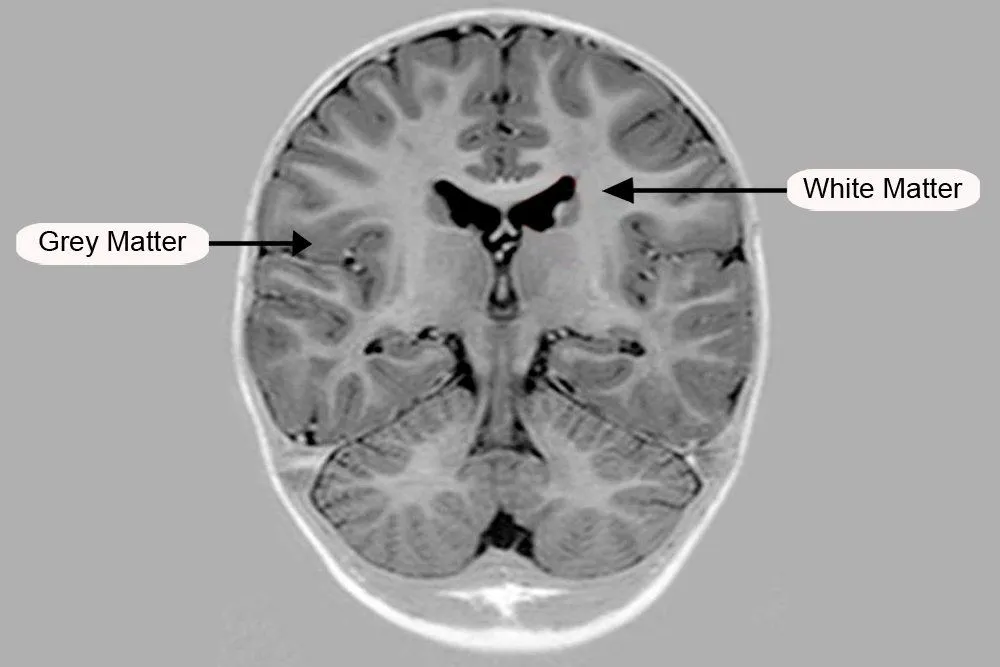

Grey And White Matter Of The Cerebrum

The cerebrum is divided into two parts, the outer grey matter covering the surface of the cerebrum called the cerebral cortex and the inner medullary region called the white matter.

The cerebral cortex which comes from the Latin word for bark is covered by a layer that is approximately 1/10th of an inch thick. This layer contains grooves and ridges, which increase the surface area of the cortex. There are about 20 billion neurons and over 300 trillion synapses in the cortex alone. An increased amount of surface area, therefore, allows for more neurons to be present.

One must have heard the term “grey cells” before, especially fans of Hercule Poirot. The fictional detective often referred to them as his, “little grey friends”. These refer to the cells in the cerebral cortex where the many neurons lack myelin sheath covering. The myelin sheath is a fatty covering around the axons of cells which give a whitish appearance to the inner medullary regions of the cerebrum.